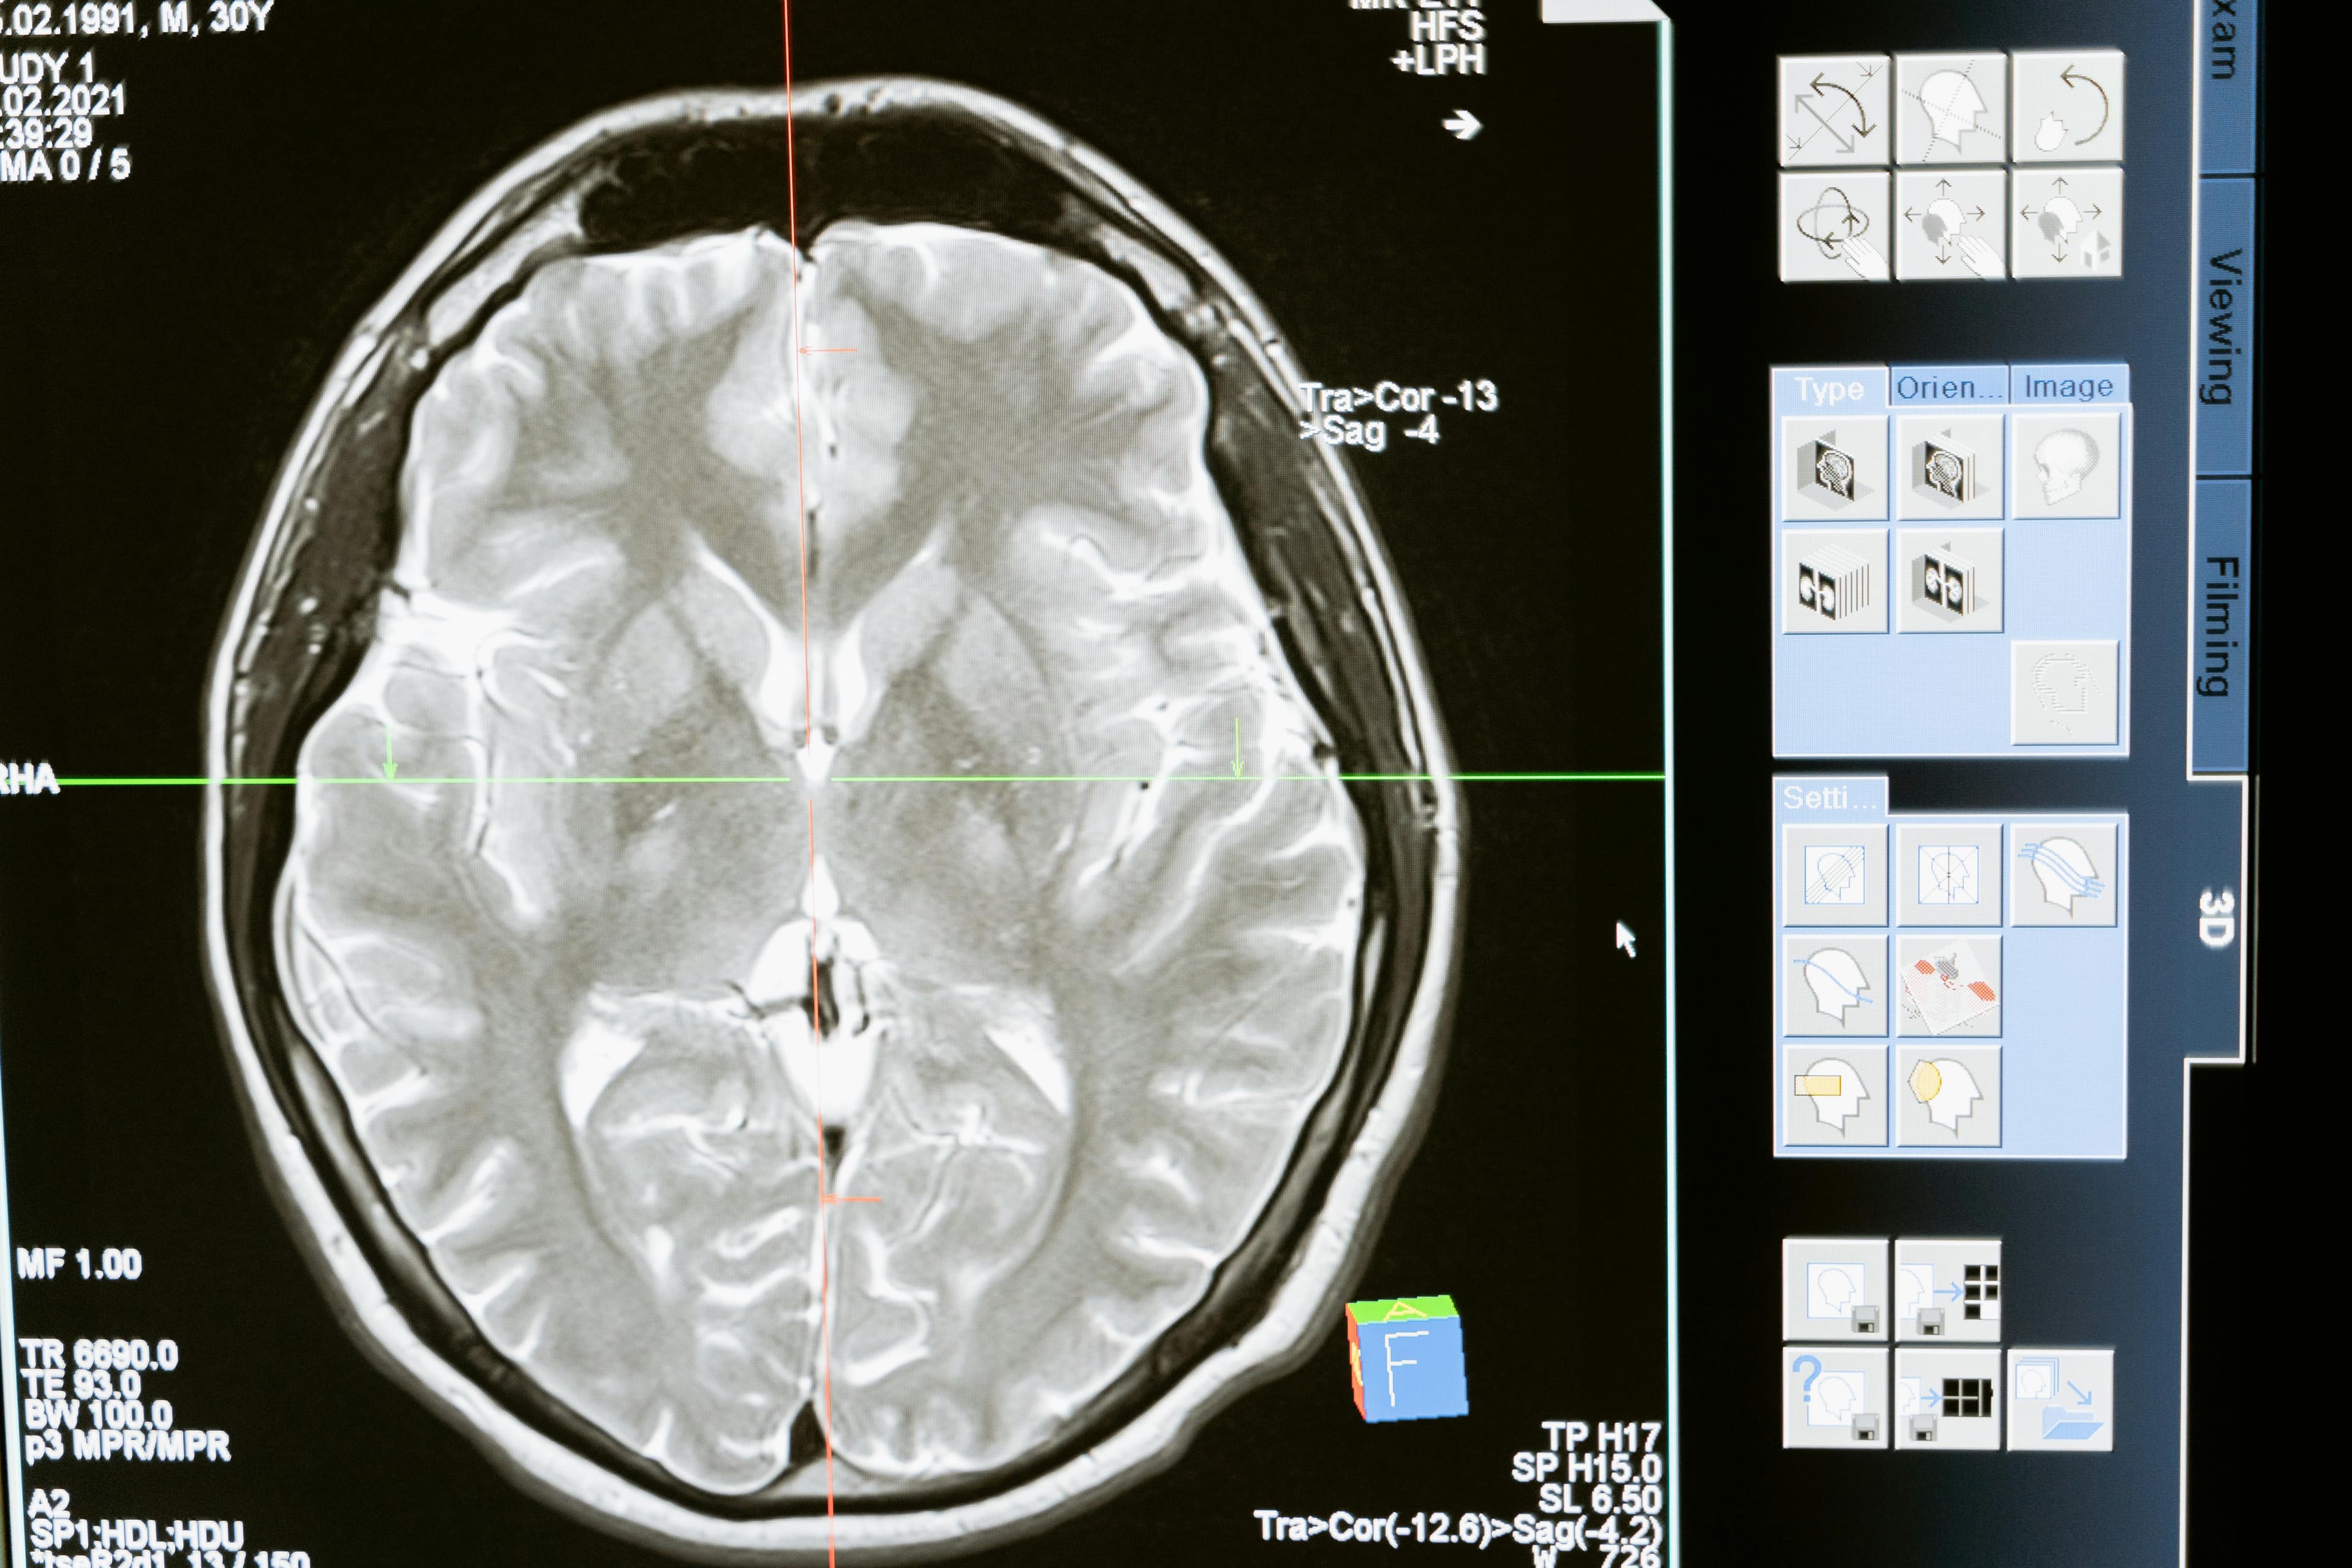

MRI technology is essential in educating patients and their families about brain trauma. At Brain Mapping Solutions, our detailed MRI scans provide valuable insights into the extent and impact of brain injuries, helping individuals understand their condition better.

At Brain Mapping Solutions, we use advanced MRI technology to provide detailed insights into brain injuries. We also offer educational resources and support to help individuals understand their condition and the importance of early diagnosis and treatment.